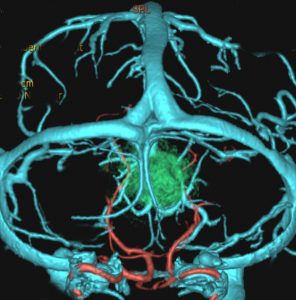

後頭下からみた腫瘍(緑)です。正中に大きな架橋静脈 vermian veinがあります。

この腫瘍を後頭下開頭で摘出しようとすれば,小脳虫部と右小脳半球の間をかなり長く縦切開しなければなりません。テント直下から小脳上面をたどっても腫瘍の上端は見えても摘出は不可能です。ですから,必然的にアプローチは後頭開頭経テント法 occipital transtentorial approachとなります。